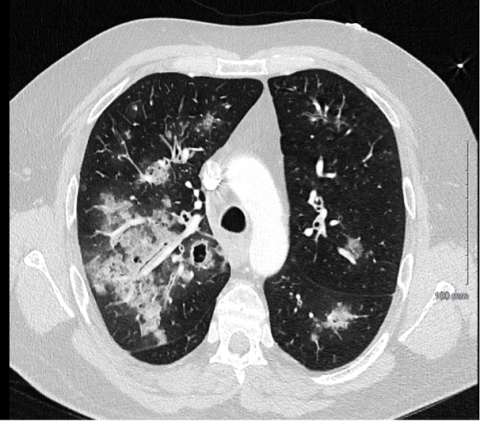

Un patient de 47 ans, cariste en activité, aux principaux antécédents d’asthme intermittent et de diabète de type 2 sous Metformine, se présente aux urgences pour une dyspnée d’apparition brutale accompagnée d’une douleur thoracique et d’une rhinorrhée évoluant depuis 3 jours. Les constantes sont normales en dehors d’une fébricule (38°C), l’examen clinique met en évidence des crépitants bilatéraux suspendus, le bilan biologique est sans particularité en dehors d’un syndrome inflammatoire biologique, les D-dimères et la troponinémie sont normaux. La radiographie thoracique met en évidence des opacités alvéolaires péri-hilaires. Un traitement par Amoxicilline, corticothérapie systémique et bronchodilatateurs est prescrit en ambulatoire.

Vingt quatre heures plus tard, le patient se présente à nouveau aux urgences pour majoration de la dyspnée et apparition d’une hémoptysie de faible abondance. A son admission il est fébrile (38.4 °C), tachycarde, normotendu sans signe d’hypoperfusion périphérique, en détresse respiratoire sous oxygénothérapie conventionnelle à 15L/min. Le bilan biologique est sans particularité en dehors d’une élévation des d-dimères (5790 ng/ml) et un syndrome inflammatoire biologique (CRP 300 mg/L, hémogramme normal à l’exception d’une lymphopénie à 0.55 G/L). La bandelette urinaire révèle une croix de protéinurie, pas d’hématurie, pas de leucocyturie. Il n’y a pas de signe clinique d’insuffisance ventriculaire droite, l’échocardiographie ne montre pas d’élément en faveur d’une élévation des pressions de remplissage des cavités gauches ni de cœur pulmonaire, l’examen clinique cutanéo-muqueux, articulaire, opthalmologique, ORL ne met pas en évidence d’élément évocateur d’une maladie de système.

Un angioscanner thoracique est réalisé éliminant une embolie pulmonaire. En voici une coupe :